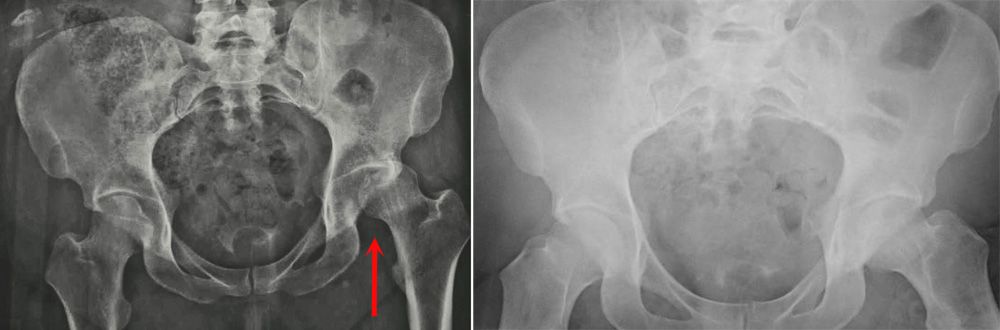

X-rays of a dislocated hip before and after reduction

(Left) This X-ray, taken from the front, shows a patient with a posterior dislocation of the left hip. (Right) Normal alignment after the hip has been reduced.